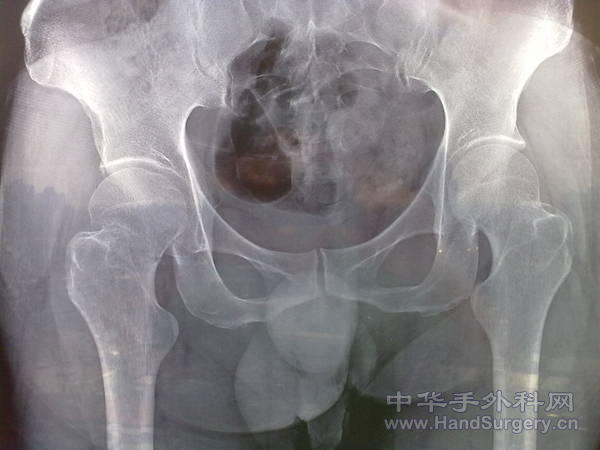

[其他] 股骨颈骨折三根钉治疗一例

第二张是术后1年的照片

嵌插骨折对吗??

应该位置比较稳定,是老年人吗??

患者78岁 男性